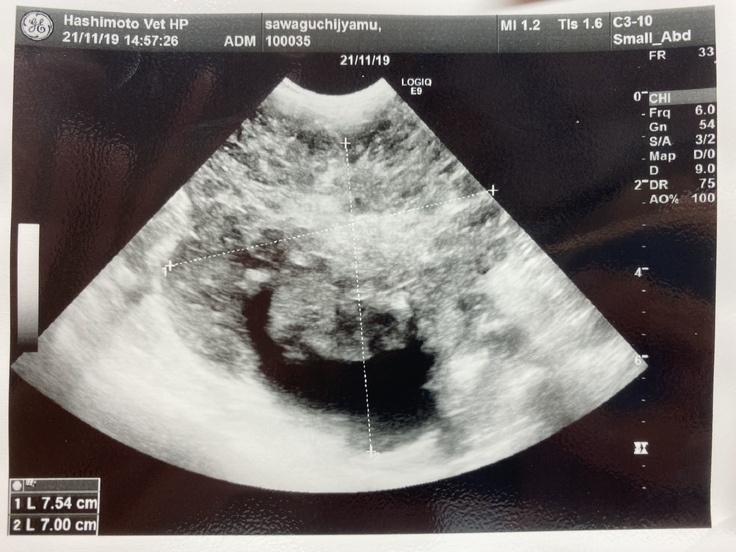

ジャムは先月、病院で腎臓がんの疑いがあると言われました。手術ができるかなどの検査をしに岐阜大の動物病院まで行きました。そこで、腫瘍が大きすぎるしいろんな血管や臓器を巻き込んでしまっているため、手術は難しい。手術したとしても余命はほとんど変わらないと言われました。できる治療は放射線治療、抗がん剤、今までやっていた炎症を抑える薬を飲む。治療はとても限られてしまうそうです。放射線治療は苦しむイメージがあるしやるか迷ったのですが、いろいろ検索していると1年も生きるのは難しいと言われていた子が3年生きたというのがあったり、岐阜大の医療機器は最新のものだったりして、やってみようと思いました。放射線治療は約30万かかると言われました。この前の検査でも10万かかりました。腫瘍に圧迫されて食欲がなくなったりするのを緩和するために放射線をがんに当てて小さくするということを行います。金銭面で苦しくなっているので、みなさんの力を借りたいと思いました。

🐶資料